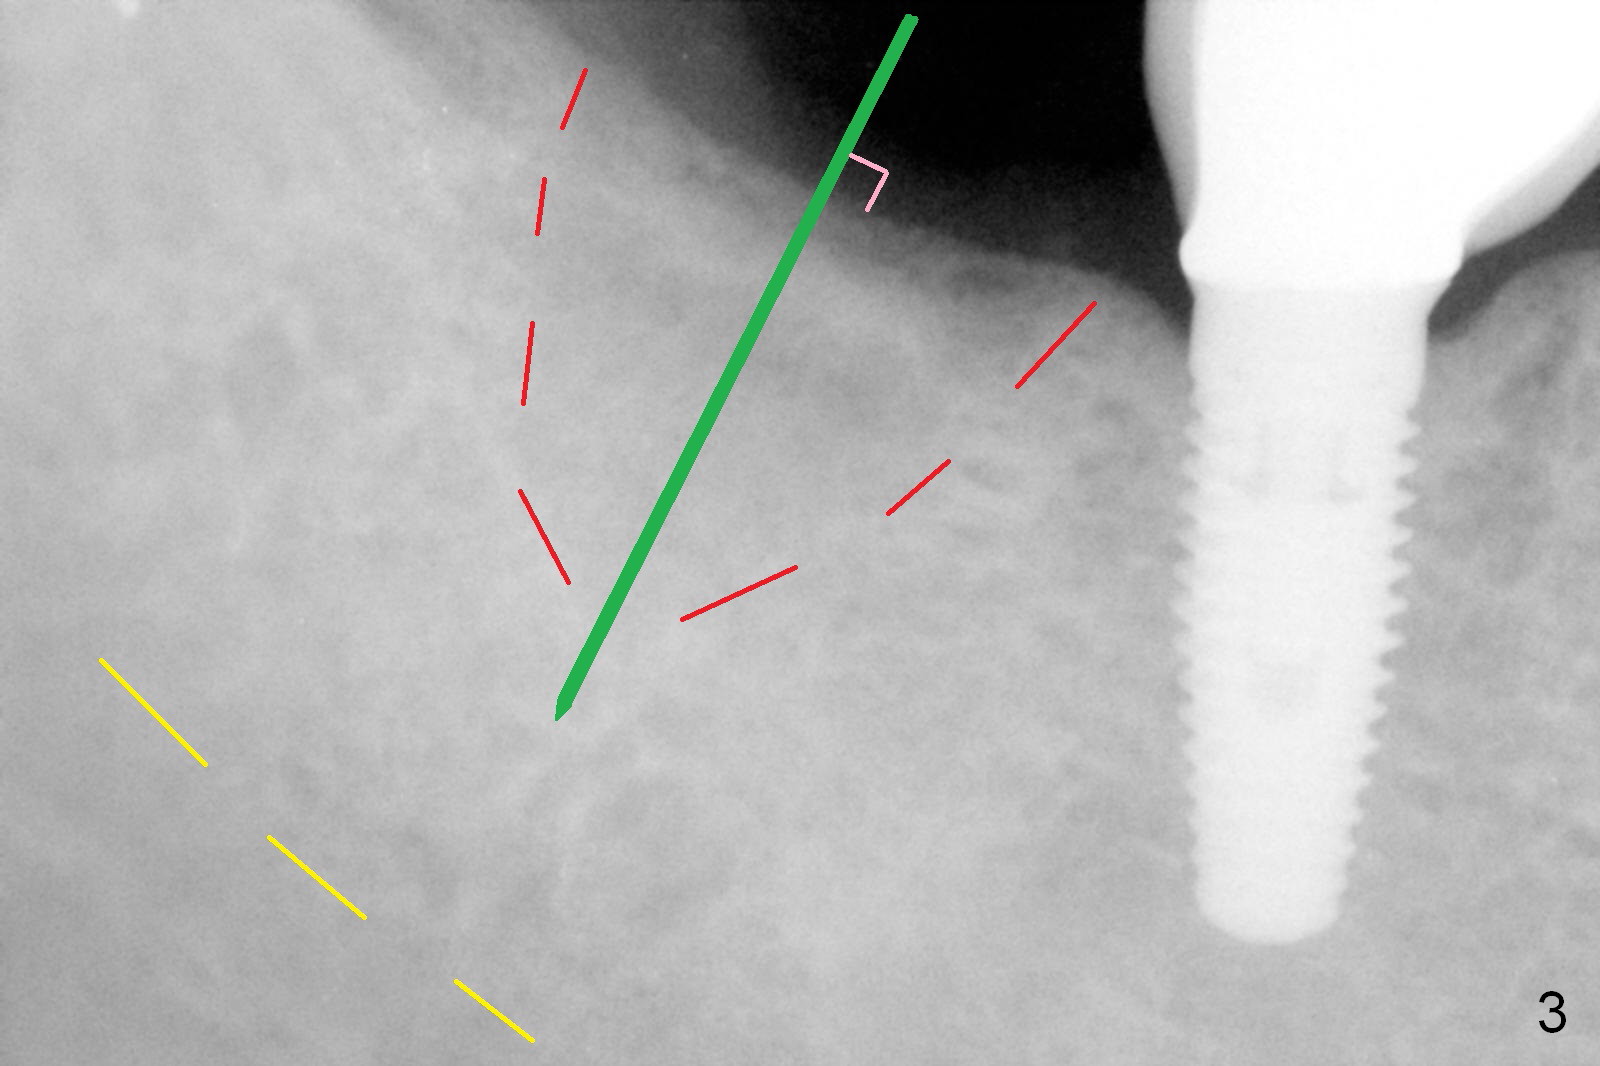

A 62-year-old woman requests #31 implant placement ~ 1 year post extraction (Fig.1). The opposing tooth (#2) appears to have not supraerupted. The socket outline at #31 is visible (Fig.2,3 red dashed line). The initial osteotomy (green) should bisect the socket and be perpendicular to the posterior mandibular slope (pink). The stopper is set at 10 mm with sufficient clearance from the superior border of the Inferior Alveolar Canal (yellow dashed line). Take PA for confirmation and make necessary adjustment. The implant is either 5x17 mm (tissue-level) or 5x13 or 14 mm (bone-level).